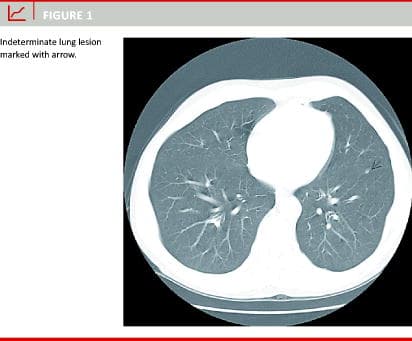

The patients were scanned with a single slice helical scanner (General Electric high-speed CT/i). The slide thickness was 1-10 mm and intravenous contrast was used in all cases. All CT scans were described by expert radiologists. Based on their diagnosis, the patients were grouped into: 1) normal chest CT, 2) manifest lung metastases, 3) suspected malignant lesions, and 4) indeterminate or tentatively benign lesions Figure 1, e.g. fibrotic strand, pleural reaction, calcified nodule etc. These diagnoses were based on the subjective evaluation of at least two experienced radiologists at the time of the examination and not on an exact retrospective grading, as used – among others – by Kronawitter et al [5].

At the time of the CRC diagnosis, 89 of the 131 patients (68%, 95% confidence limits: 60-76) had a normal chest CT, five (4%, 95% confidence limits: 1-9) had manifest lung metastases, 11 (8%, 95% confidence limits: 4-15) had suspected malignant lesions, and, finally, 26 (20%, 95% confidence limits: 14-28) had indeterminate or tentatively benign lesions.

The size of these indeterminate chest CT lesions was median 1.1 cm (range: 0.2-3.8 cm). Thirteen patients had a single lesion and seven had more than one lesion (median: 2, range: 2-3).